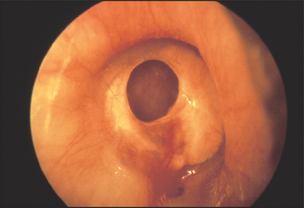

Inspect the tympanic membrane (ear drum) by introducing the speculum further into the canal in a forward but downward direction. The normal tympanic membrane is a pearly grey colour. It is ovoid in shape and semi-transparent (see Figure 38.15). The upper fifth is called the pars flaccida and the lower four-fifths are called the pars tensa. The handle of the malleus is often visible near the centre of the pars tensa. From the lower end of the handle a bright cone of light should be visible: the light reflex. The presence or absence of the light reflex is not a sensitive or a specific sign of disease (see Figures 38.16 and 38.17). Note the colour, transparency and any evidence of dilated blood vessels (hyperaemia—a sign of otitis media; see Figure 38.17). Look for bulging or retraction of the tympanic membrane. Bulging can suggest underlying fluid or pus in the middle ear. Retraction means a reduction in pressure in the middle ear and is a sign of a blocked Eustachian tube. Perforation of the tympanic membrane should be noted (see Figure 38.18).

Figure 38.18 Perforated tympanic membrane (From Mir MA. Atlas of clinical diagnosis, 2nd edn. Edinburgh: Saunders, 2003, with permission.)